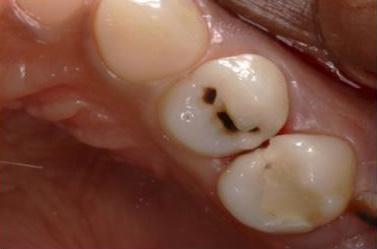

Fig. 1: Pre-operative situation with large orifice.

One of the suitable indications for FRC is the endodontically treated premolar with one big orifice and one large oval canal or deep furcation (Figs. 1-4). In such cases, an FRC can be placed as a Nayyar’s core modification5 without preparing the orifice part with Gates or Largos. The restoration can be finished as usual, directly with a conventional composite.

Upon clinical examination, caries were diagnosed in the distal area of tooth #24, and a deep caries lesion in the mesial area of tooth #25 was found to be causing irreversible pulpitis. In tooth #26, only a root remnant was present, and an extraction was planned. (Fig. 1 & 2)